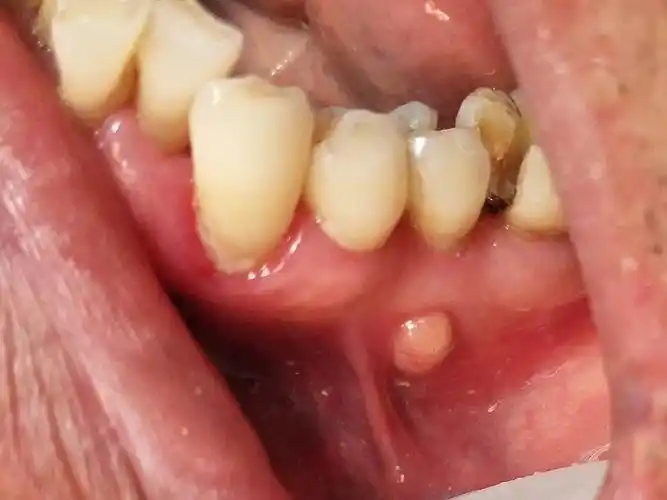

前牙外伤致根尖囊肿.总以为"牙齿"还年轻,却忽略了"囊肿"的 - 抖音

牙龈脓包别轻视,这是根尖脓肿/囊肿的一种症状,大部分的根尖囊 - 抖音

科普丨牙龈"长包"要重视,小心是根尖囊肿!

牙疼,牙龈长脓包,警惕慢性根尖牙周炎

根尖囊肿需要做根管治疗

牙齿根尖囊肿应该引起注意